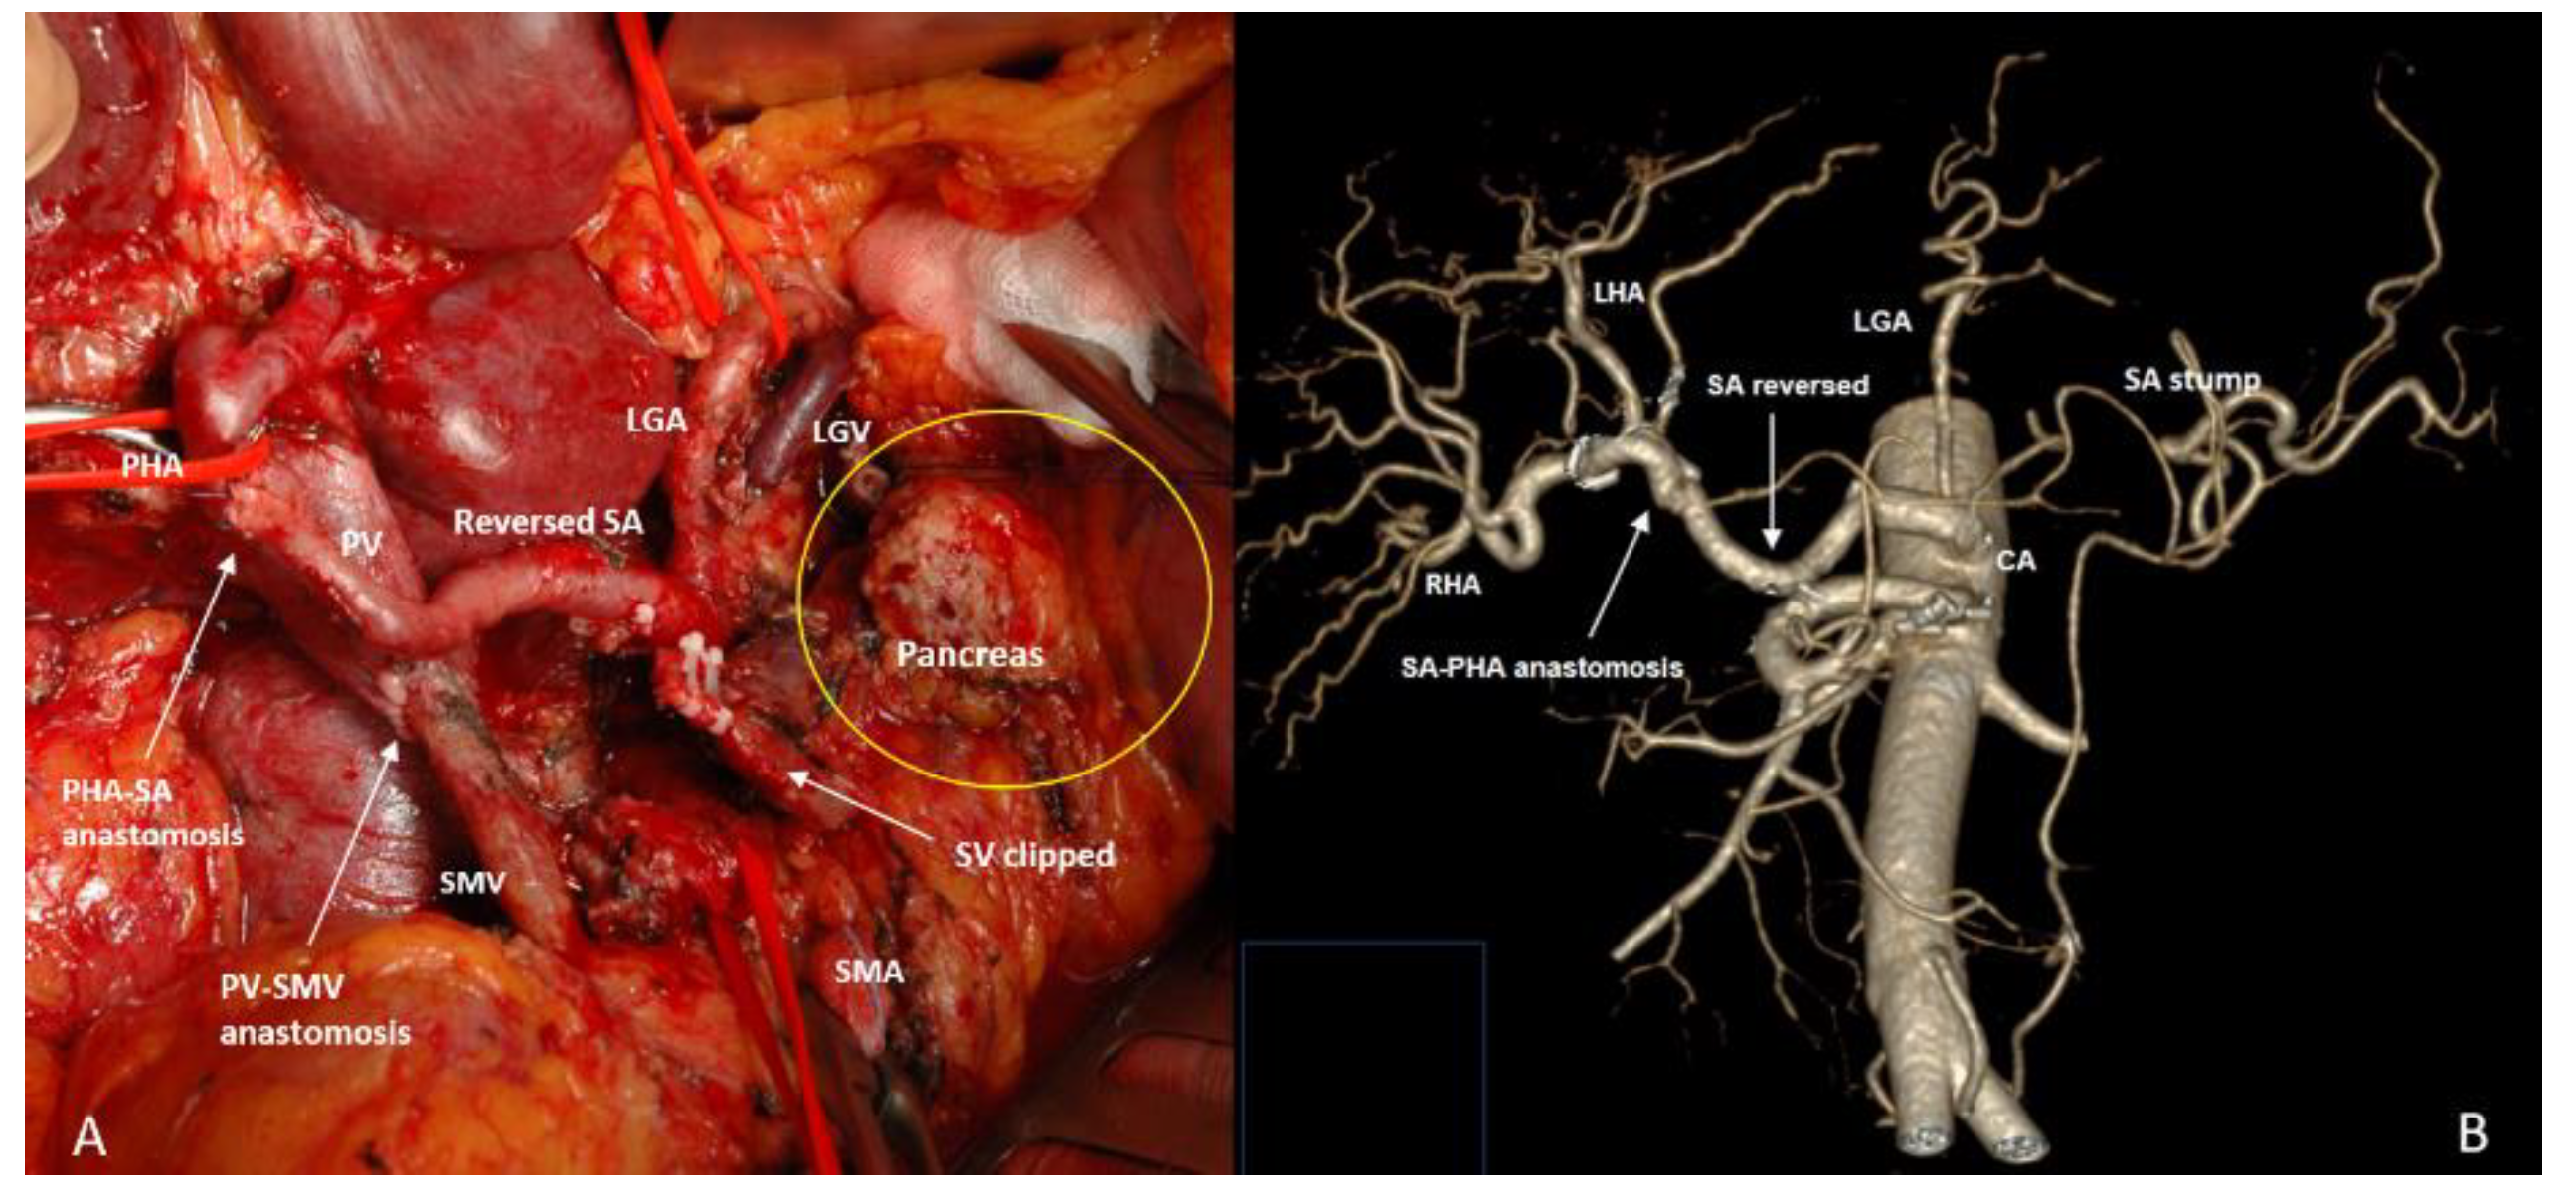

3.3. Spleen-Preserving Pancreatectomies with Resection of the Splenic Vessels, Other than Distal Resections

3.4. Spleen-Preserving Pancreatectomies with Resection of the Splenic Artery (Vessels) for Border Line Resectable and Locally Advanced Pancreatic Head Cancers